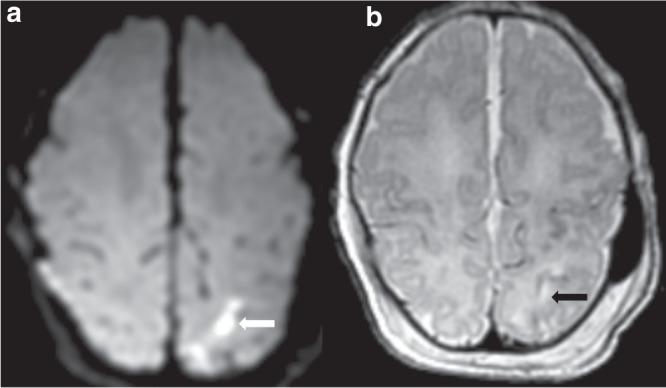

Mild hypoxic-ischemic encephalopathy (HIE) is increasingly recognized as a risk factor for neonatal brain injury. We examined the timing and pattern of brain injury in mild HIE.

This retrospective cohort study includes infants with mild HIE treated at 9 hospitals. Neonatal brain MRIs were scored by 2 reviewers using a validated classification system, with discrepancies resolved by consensus. Severity and timing of MRI brain injury (i.e., acute, subacute, chronic) was scored on the subset of MRIs that were performed at or before 8 days of age.

Of 142 infants with mild HIE, 87 (61%) had injury on MRI at median age 5 (IQR 4-6) days. Watershed (23%), deep gray (20%) and punctate white matter (18%) injury were most common. Among the 125 (88%) infants who received a brain MRI at ≤8 days, mild (44%) injury was more common than moderate (11%) or severe (4%) injury. Subacute (37%) lesions were more commonly observed than acute (32%) or chronic lesions (1%).

Subacute brain injury is common in newborn infants with mild HIE. Novel neuroprotective treatments for mild HIE will ideally target both subacute and acute injury mechanisms.

Almost two-thirds of infants with mild HIE have evidence of brain injury on MRI obtained in the early neonatal period. Subacute brain injury was seen in 37% of infants with mild HIE. Neuroprotective treatments for mild HIE will ideally target both acute and subacute injury mechanisms.